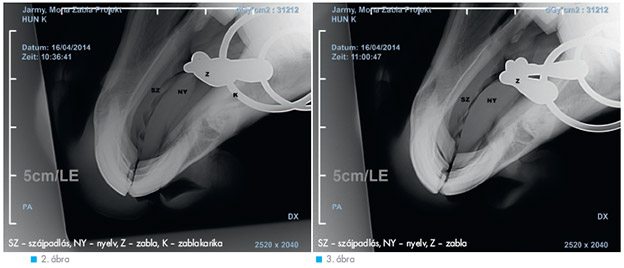

A legszélesebb körben alkalmazott zablatípus. A középső ízesülésnek köszönhetően a lovas képes a két zablakart külön-külön mozdítani, így jobb befolyást gyakorolni a ló oldalhajlítására. Bár, mint dr. Clayton kutatásai bizonyították, az egyik oldalon gyakorolt szárhatás a másik oldalon is jelentkezik – igaz, kisebb mértékben. Elterjedt vélemény, hogy a két kar a szárak húzásakor diótörőhöz hasonló hatást fejt ki, amikor a csuklónál jobban meghajlik. Ezzel egyrészt szorítja a ló nyelvét, másrészt a hegye élesen nyomja a kemény szájpadlást. E kényelmetlenség miatt tátják el egyes lovak a szájukat, de küzdhetnek ellene a szárba dőléssel is. Az effajta nemkívánatos hatás mérsékelhető vagy elkerülhető a kétszer tört, illetve a megfelelően hajlított szájrésszel. Ezt a feltételezést cáfolják a kutatások, és mint az a 2. ábrán látható, ha húzásba kerülnek a szárak, a szájrész jobban benyomódik a nyelvbe, ezáltal a csukló messzebb kerül a szájpadlástól. A karika lehetővé teszi, hogy a szájrész szabadon mozogjon, így a ló a nyelvét használva különböző helyzetekbe mozdíthatja a szájrészt, talán, hogy változtasson a nyomás alatt lévő területeken.

Továbbfejlesztett változata esetében az összekötő elem nem lapos, hanem rögbilabda alakú, és el van forgatva, hogy a csukló részek egyike se nyomja a ló szájpadlását. A 3. ábrán látható, hogy nem kerül olyan közel a szájpadláshoz, mint az egyszer tört zabla csuklós része. A szárak meghúzásakor a nyelv összenyomásával a teljes szájrész eltávolodik a szájpadlástól. Tovább erősítve a befolyást, a középső rész felfelé gördül a nyelv felületén. Igen sok ló számára kényelmes ez a fajta zabla és jól dolgozik vele, ami minden bizonnyal a középső rész és a szájpadlás nagy távolságának, illetve a finom gömbölyített kiképzésének köszönhető.